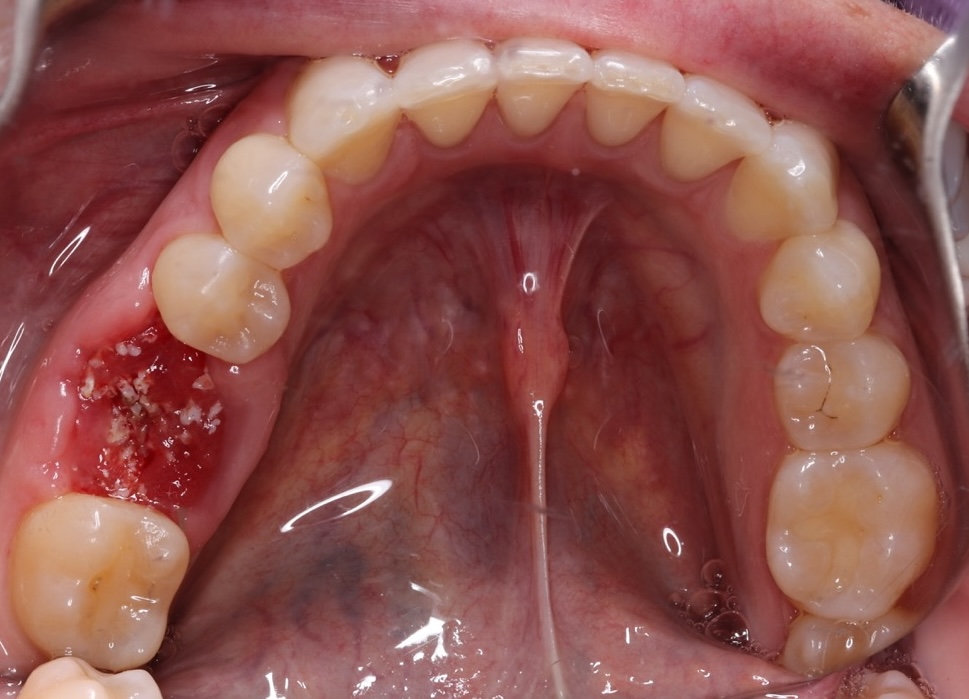

Comprehensive biological oral surgery case showing Tooth #30 extraction, guided bone regeneration, implant placement, and crown restoration using Groton Wellness’ minimally invasive, biologically supportive protocols.

This case follows Jennifer, a 47-year-old female, through the full biological treatment sequence: from extraction of Tooth #30 to guided bone regeneration, implant placement, and final crown restoration. Each step was planned with CBCT-based visualization and executed using open wound healing principles to support long-term oral and systemic wellness.

May 14, 2024Extraction of Tooth #30 with biological protocols.

Visual Case Progression

All clinical images are shown at a consistent size for easy comparison.